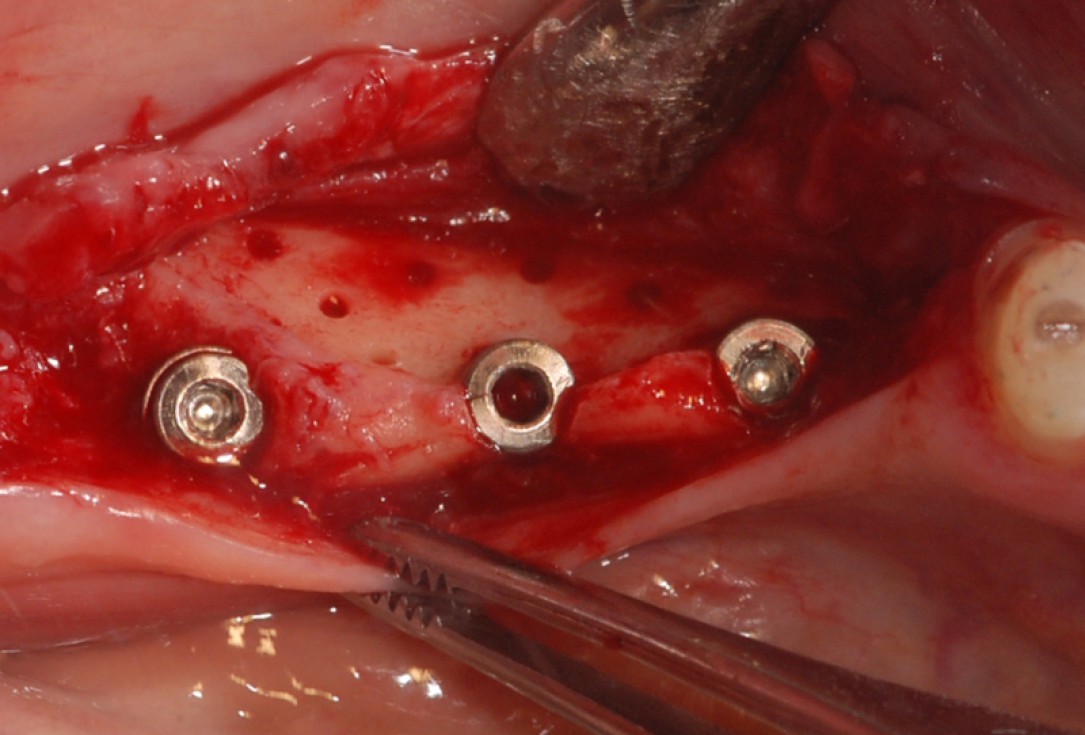

Three implants placed in a narrow posterior mandible